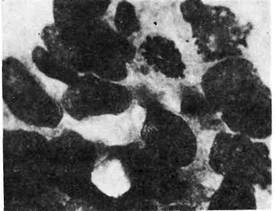

4. Слизистый (коллоидный) рак — аденогенная карцинома, клетки

Рис. 141. Слизистый (кол-

пизма (извращенное

слизеобразование).

Раковые клетки продуци-

руют огромное количество

слизи и в ней погибают.

Опухоль имеет вид сли-

зистой или коллоид-

ной массы, в которой

микроскопически обнару-

живаются атипичные клет-

ки (рис. 141). Слизистый

(коллоидный) рак — одна

из форм недифференциро-

ванного рака.